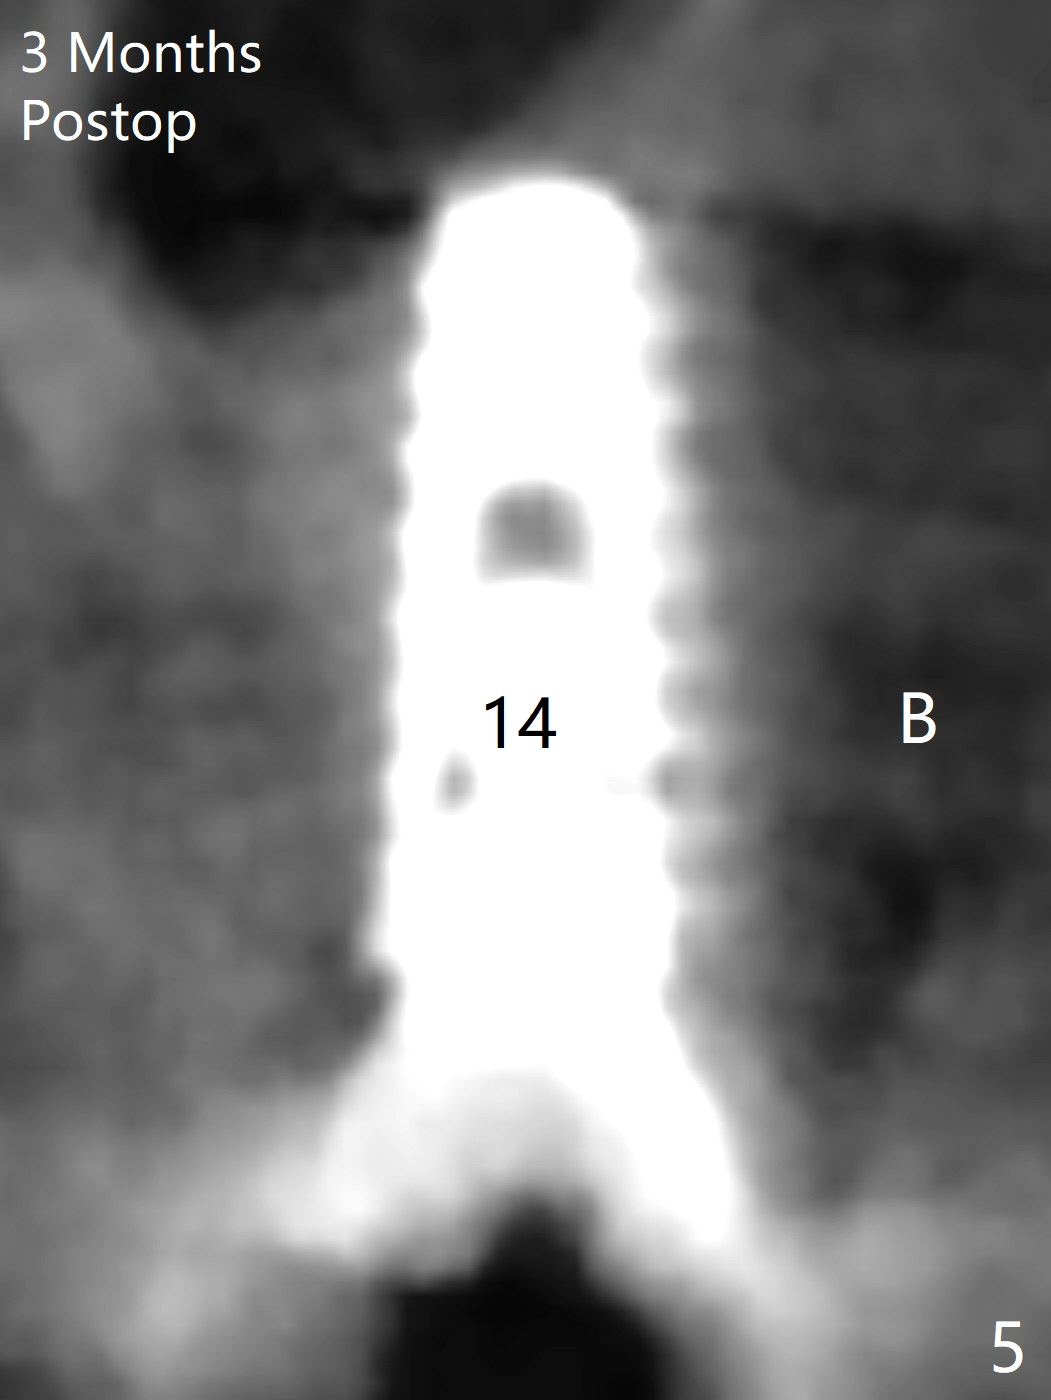

Initial osteotomy in the septum of the tooth #14 is 9 mm, approximately 2 mm from the sinus floor (Fig.1).  Subsequent osteotomy depth is 11 mm, followed by insertion of a 4.5x11 mm dummy implant (Fig.2).  After use of Magic Drill (MD) 4.8 mm for 9 mm, a 5x11 mm IBS implant is placed with sinus lift without additional bone graft (Fig.3 *).  In contrast, autogenous bone (from MD) and Vanilla Graft are meticulously placed in the remaining socket (+) before and after placement of a 6.5x5.7(2) mm abutment.  An immediate provisional is fabricated to close the sockets.  There is buccal tenderness 1-3 months postop.  There is distopalatal implant thread exposure.  A healing abutment (5.5x2 mm) is placed.  CT confirms thin buccal plate (Fig.4,5).  It appears that the implant should have been as palatal as possible.  The tenderness remains for the next 2 weeks.  When the healing abutment is removed, the implant seems to have been placed shallow, ~ 1 mm subgingival (Fig.6).  With local anesthesia, the implant is reversed to clean the coronal threads with Titanium brush and copious irrigation (Fig.7).  The implant is then placed ~4 mm subgingival (Fig.8) and slightly subcrestal (Fig.9,10).  It appears that the postop bone loss (Fig.9 *, as compared Fig.1,2) makes the implant look to be placed too shallow.  When the implant is being placed deeper, the buccal plate feels intact.  The early periimplantitis is apparently due to postop bone loss more than buccal placement, although certain degree of buccal bone resorption must occur.  A 6x4 mm healing abutment is placed.  Left facial swelling develops 2 days post implant elevation (Fig.11,12, as compared to preop (Fig.13)).  The left maxillary sinus cloud (Fig.12) appears to be a false positive finding, since the same feature exists prior to implant elevation (Fig.13).  Both sinuses look clear prior to implant elevation (Fig.14).  Amoxicillin switches to Augmentin and Flagyl, since the patient is reluctant to have the implant removed.  Finally the sinus infection is under control.  The patient feels left facial swelling 9 months postop (5 months post elevation) and reports left nasal discharge ~ 1 month earlier.  There is mild buccal plate tenderness.  The implant seems to be buccally placed (Fig.15,16), although there is no significant change radiographically (Fig.17).  The implant is removed with bone graft (Fig.18 *).  To avoid complication and failure, an immediate implant at the upper 1st molar should be short and placed deep.